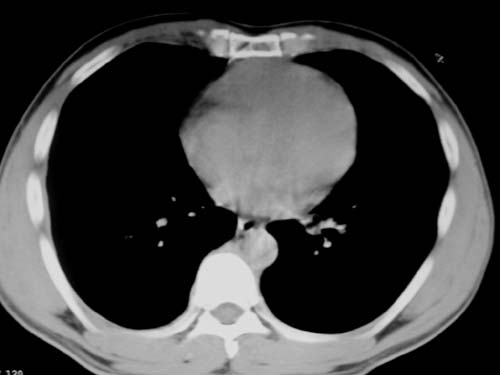

标题: CT19540: 31岁。自述结核性胸水治疗两个月后,在外院拍x线发 [打印本页]

标题: CT19540: 31岁。自述结核性胸水治疗两个月后,在外院拍x线发

右侧胸壁结节状软组织影伴相应肺叶内受侵,伴右侧胸腔积液。考虑:结核性可能大。

支持 右侧胸壁结节状软组织影伴相应肺叶内受侵,伴右侧胸腔积液。考虑:结核性可能大。

右侧胸壁结节状软组织影伴相应肺叶内受侵,伴右侧胸腔积液,结合临床,首先考虑结核。

考虑结核性胸膜炎,胸膜肥厚,不除外胸膜间皮瘤可能,建议复查。

1)考虑右侧结核性胸膜结节。2)右侧胸膜增厚+包裹性胸腔积液。